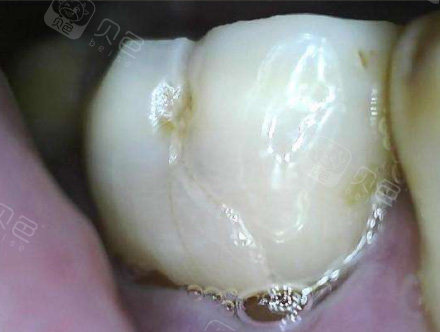

牙隐裂照片

图片尺寸440x332